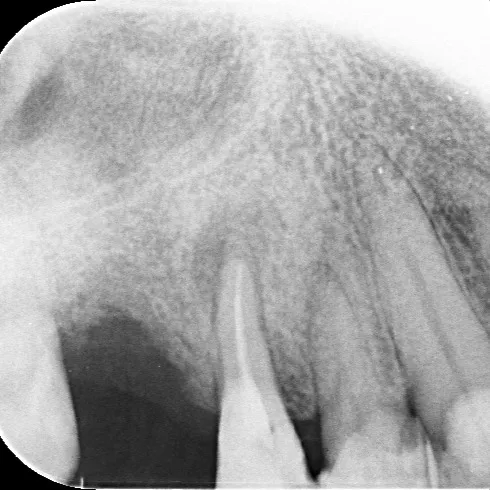

これは歯の神経を取った後の根管治療、その終わり際の根充と呼ばれる治療をしてる状態です😮

拡大鏡でしっかり確認しながら、ガッタパーチャポイントというゴムみたいな素材を根につめているところですね🧐

👉 スワイプして、治療後の根管治療の状態をレントゲン確認!